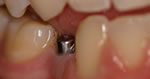

Step Two:

The dental implant "anchor"

is put into place. |